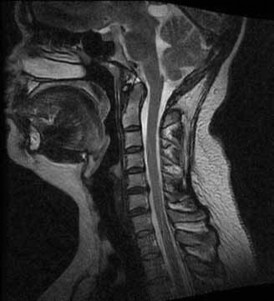

Figures A and B are pre-operative and intra-operative radiographs of a 67-year-old male that has undergone a left total hip arthroplasty under general anesthesia. The patient had no motor deficits preoperatively. During the operation, the trial acetabular and femoral components were positioned and reduced with no complication. Intraoperative leg lengths were equal. Before implanting the real components, the surgeon and anaesthesiologist performed a wake up test, which revealed that the patient was unable to dorsiflex the left foot. What would be the most appropriate next step in the management of this patient?

This patient has undergone a left THA with significant leg lengthening. The biggest concern is stretch to the sciatic nerve. The most appropriate step at this stage would be to perform a subtrochanteric osteotomy to decrease leg length and sciatic nerve stretch.

Patients with DDH that have undergone a large limb-lengthening procedure are at a greater risk due to the significant stretch of the sciatic nerve. Intraoperative procedures that have been shown to prevent this outcome include good pre-operative planning, limb lengthening